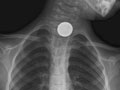

A chest X-ray is a picture of the chest that shows your heart, lungs, airway, blood vessels, and lymph nodes. A chest X-ray also shows the bones of your spine and chest, including your breastbone, your ribs, your collarbone, and the upper part of your spine.

- Find foreign objects, such as coins or other small pieces of metal, in the tube to the stomach (esophagus), the airway, or the lungs. A chest X-ray may not be able to see food, nuts, or wood fibers.

- A foreign object is seen in the esophagus, breathing tubes, or lungs.